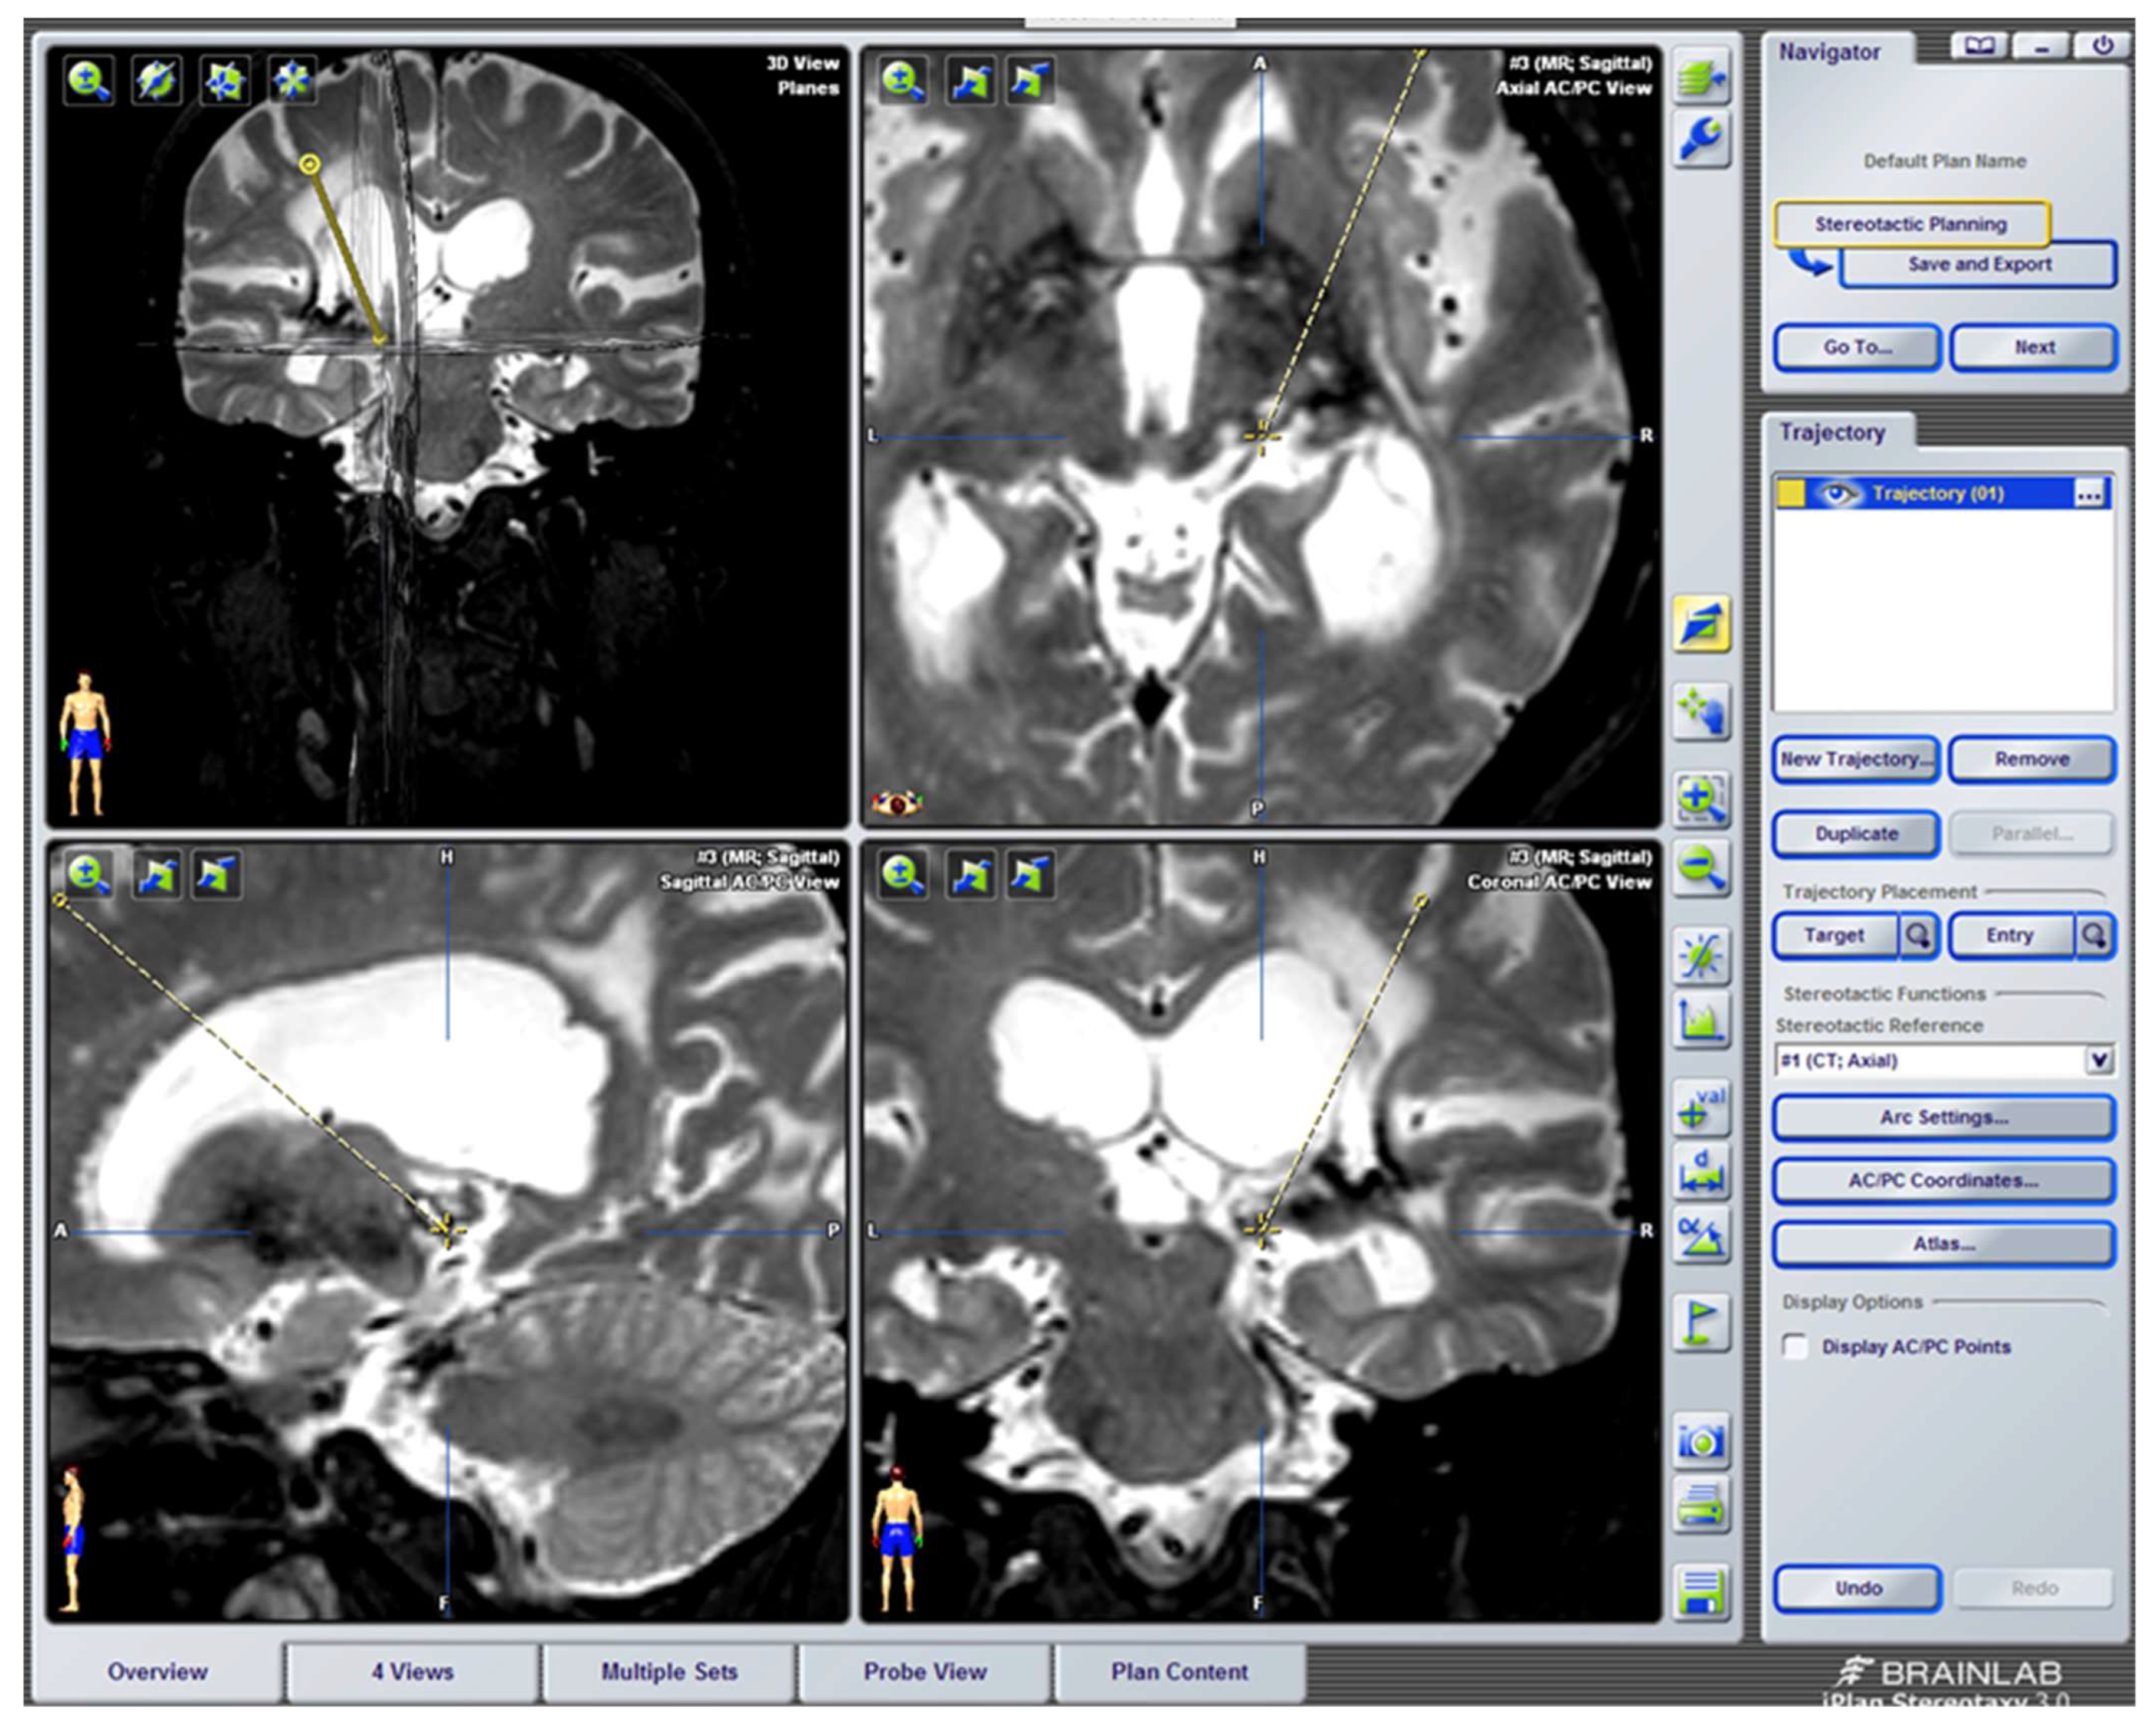

- Regarding the implantation of intracranial electrodes, there have been great advances that have modified the surgical placement techniques and improved intra- and postoperative control. We refer to the use of CT and MRI fusion programs [249] and new neuronavigation software, including the different stereotactic atlases [250]. In addition, improvements in intraoperative neurophysiological exploration, through prior recording with microelectrodes, compared to classic stimulation with implantable macroelectrodes, should also be mentioned [251]. Microelectrode recording and stimulation are very useful at the level of the sensory thalamic nuclei, in which there is a somatotopic distribution; however, it is not as useful as at the PAG-PVG level [250].